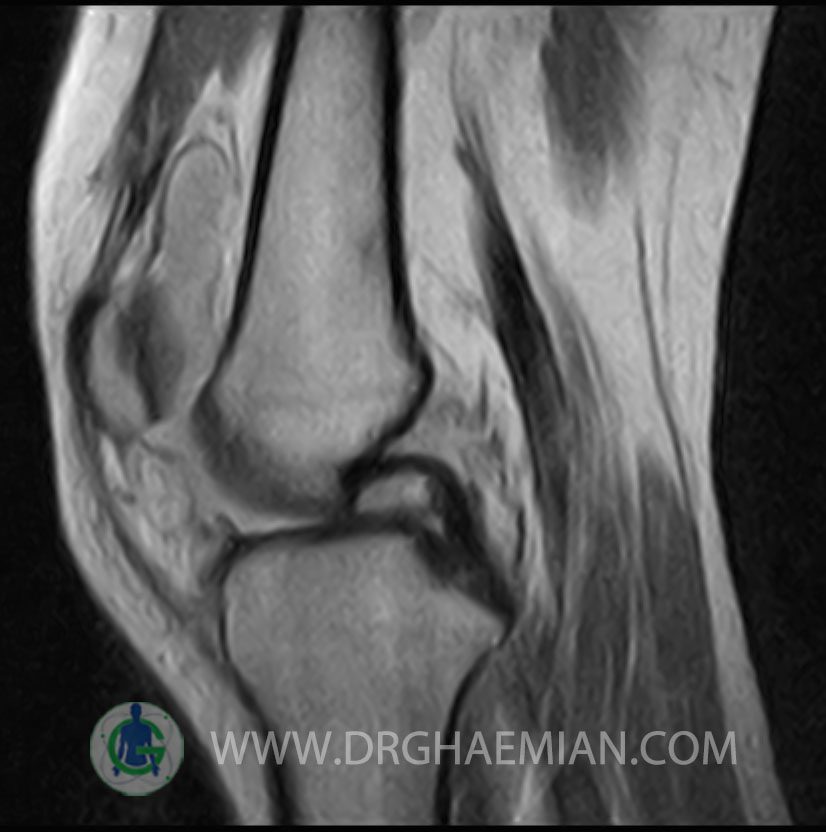

RIGHT KNEE MRI

(Without contrast)

Technique: Sagittal T1, T2 , Axial GE , coronal & sagital fatsat .

– Knee joint effusion with soft tissue swelling around the knee

– Grade 2 signal change in P.H. of medial meniscus with partial tearing of posterior root & meniscal extrusion

– Grade 2 signal change in P.H. of lateral meniscus with meniscal extrusion

– Complete tearing of ACL ( femoral detachment ) with bone bruise in plateau of tibia

are seen